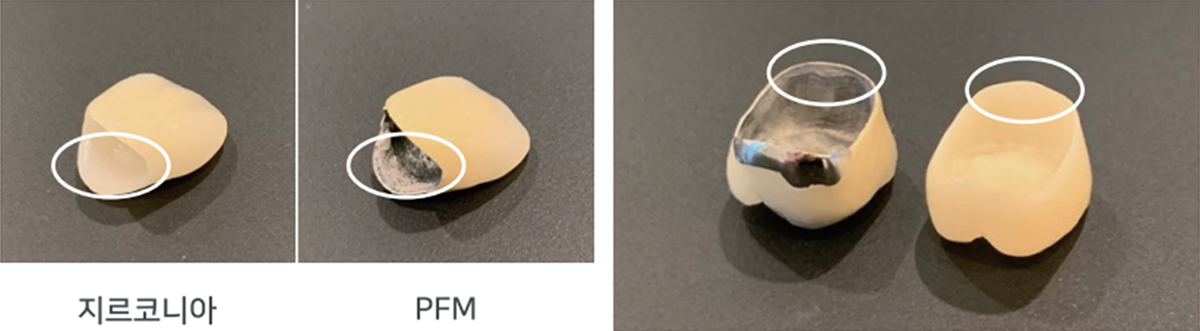

같은 치아색이지만 PFM은 내부에 금속이 있어 더 두껍고 잇몸라인이 검게 보일 수 있습니다.

신경치료하지 않은 자연치인 경우 지르코니아가 치아 삭제량이 더 적어 치아 건강에 좋습니다.